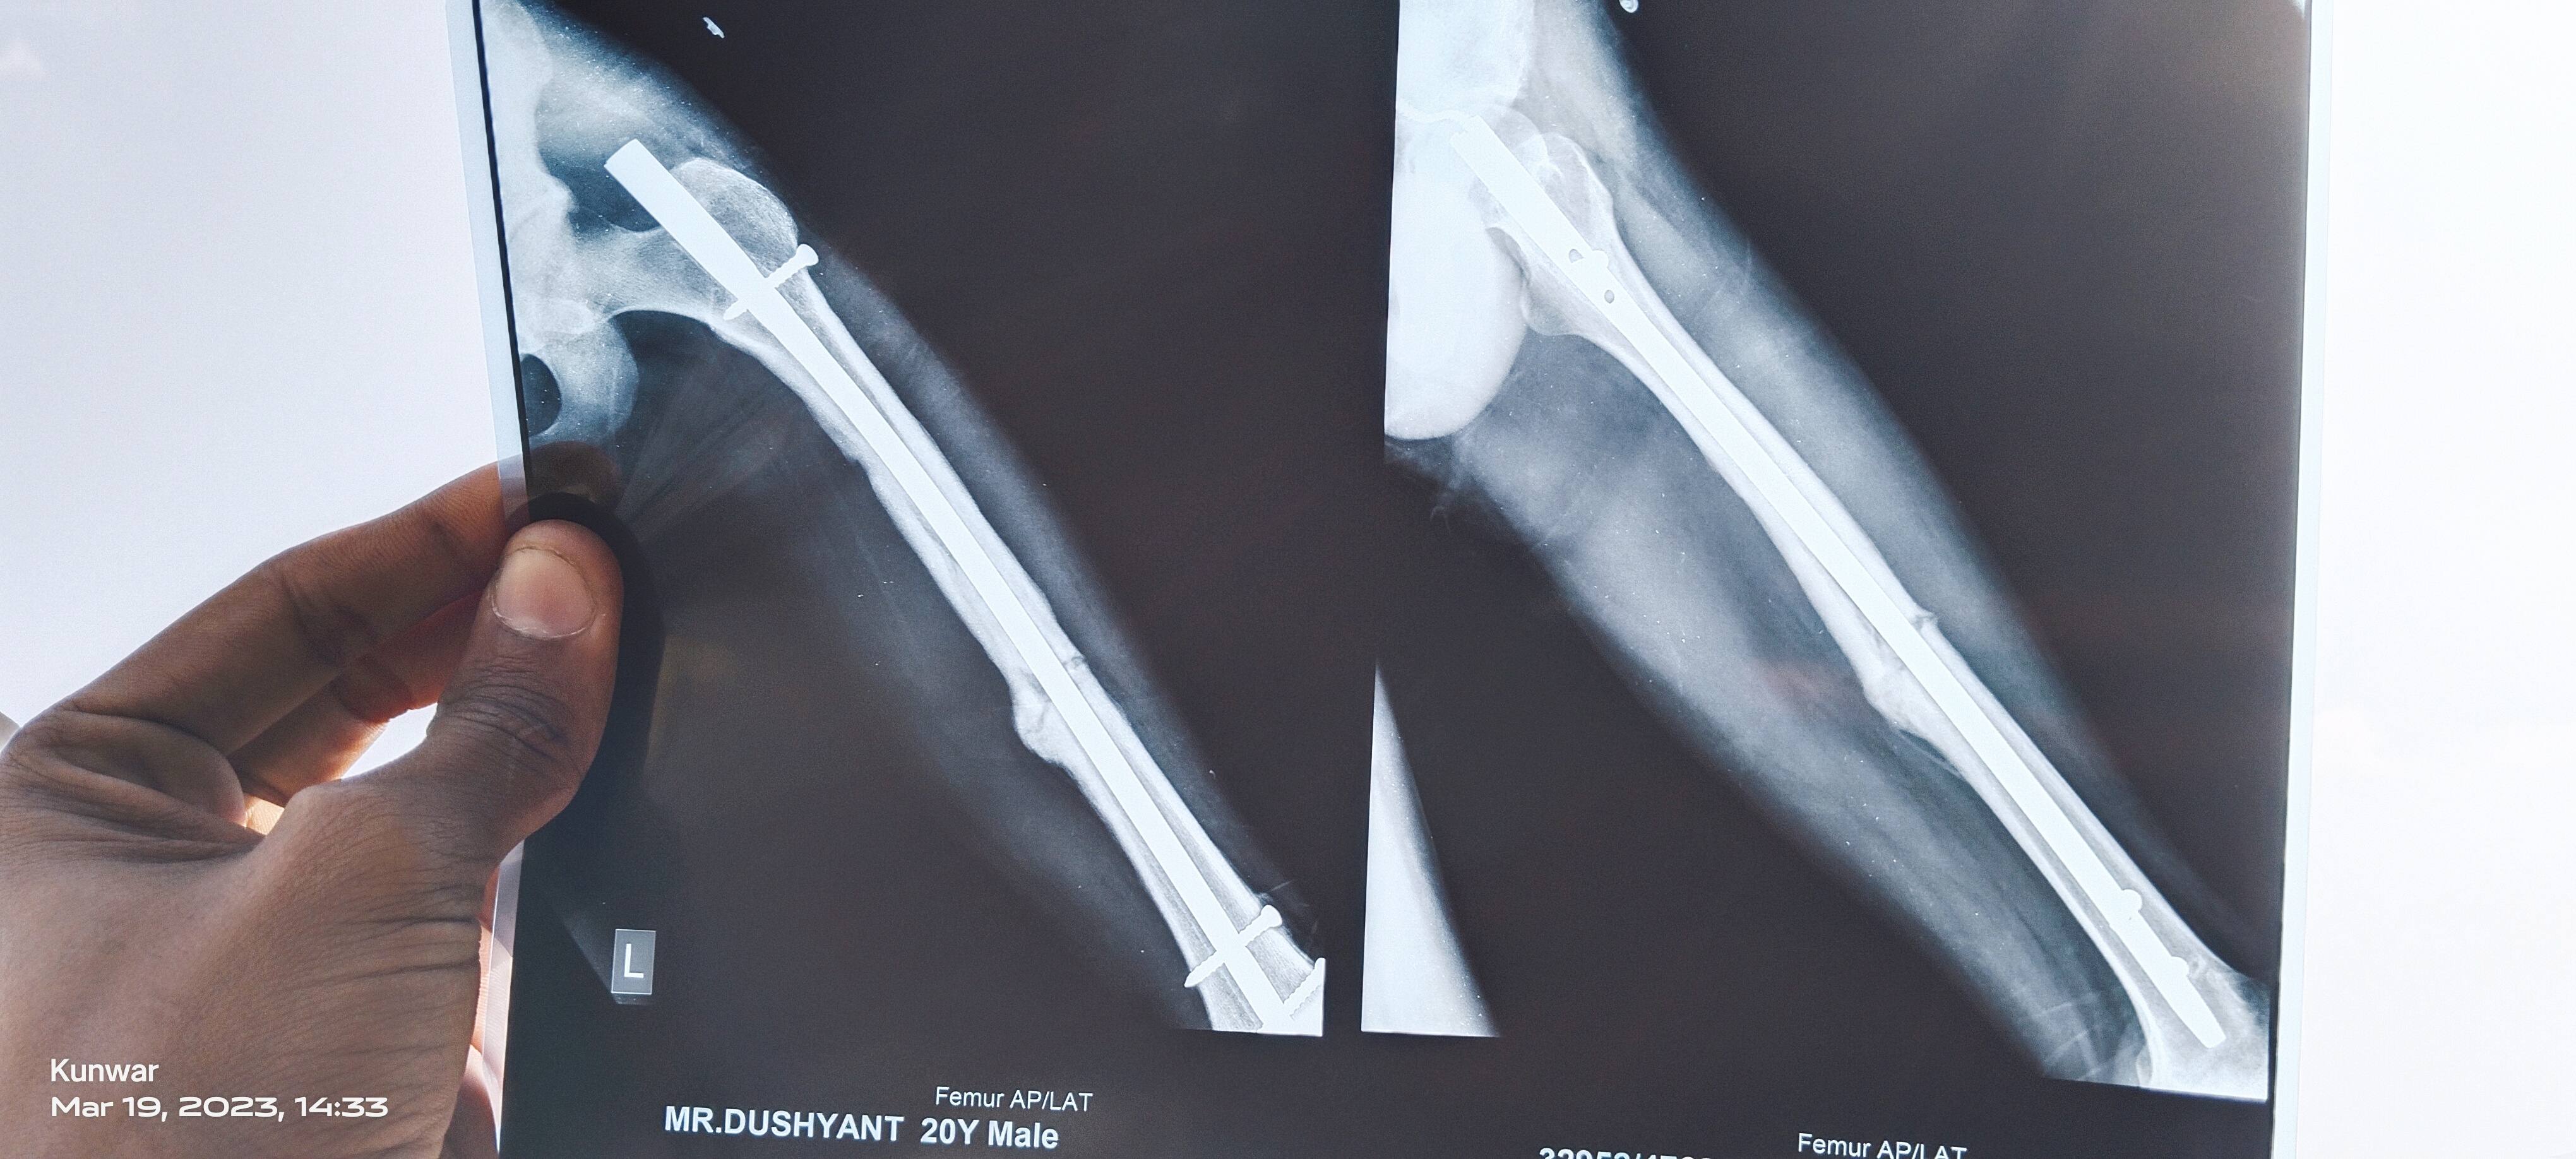

Dushyant from.palwal

sir this one is latest x ray on 7 month 10 days